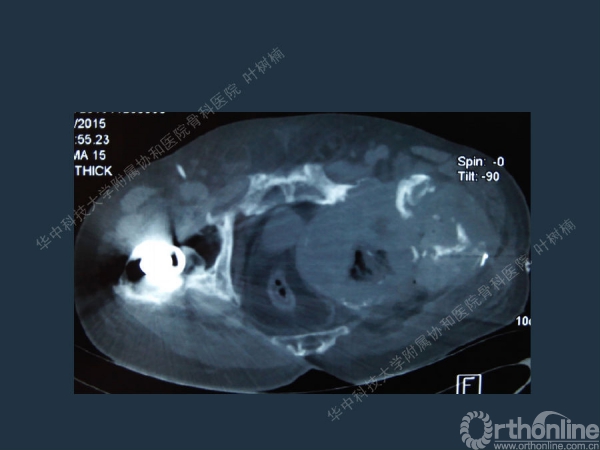

股骨侧翻修

髋臼缺损的处理